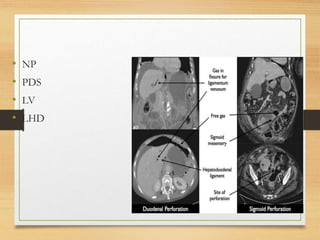

• NP

• PDS

• LV

• LHD